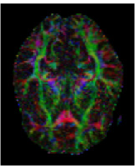

The first eigenvector , also called principal diffusion vector, of describes the predominant diffusion direction, which is parallel to the orientation of the corresponding underlying WM fiber system. Figure 3 shows a visualization of the color-coded MR-DTI data with ellipsoids. The predominant diffusion direction can be directly related to a Green (G), Red (R) and Blue (B) digital color triple. The convention in which the G, R and B color components represent the directions is as follows:

| (6) |

The RGB color-coded directionality maps provide an indication of the direction in which water diffusion is the highest and improve the visibility of different WM fiber bundles.

![]() |

| (a) | (b) | (c) | (d) |